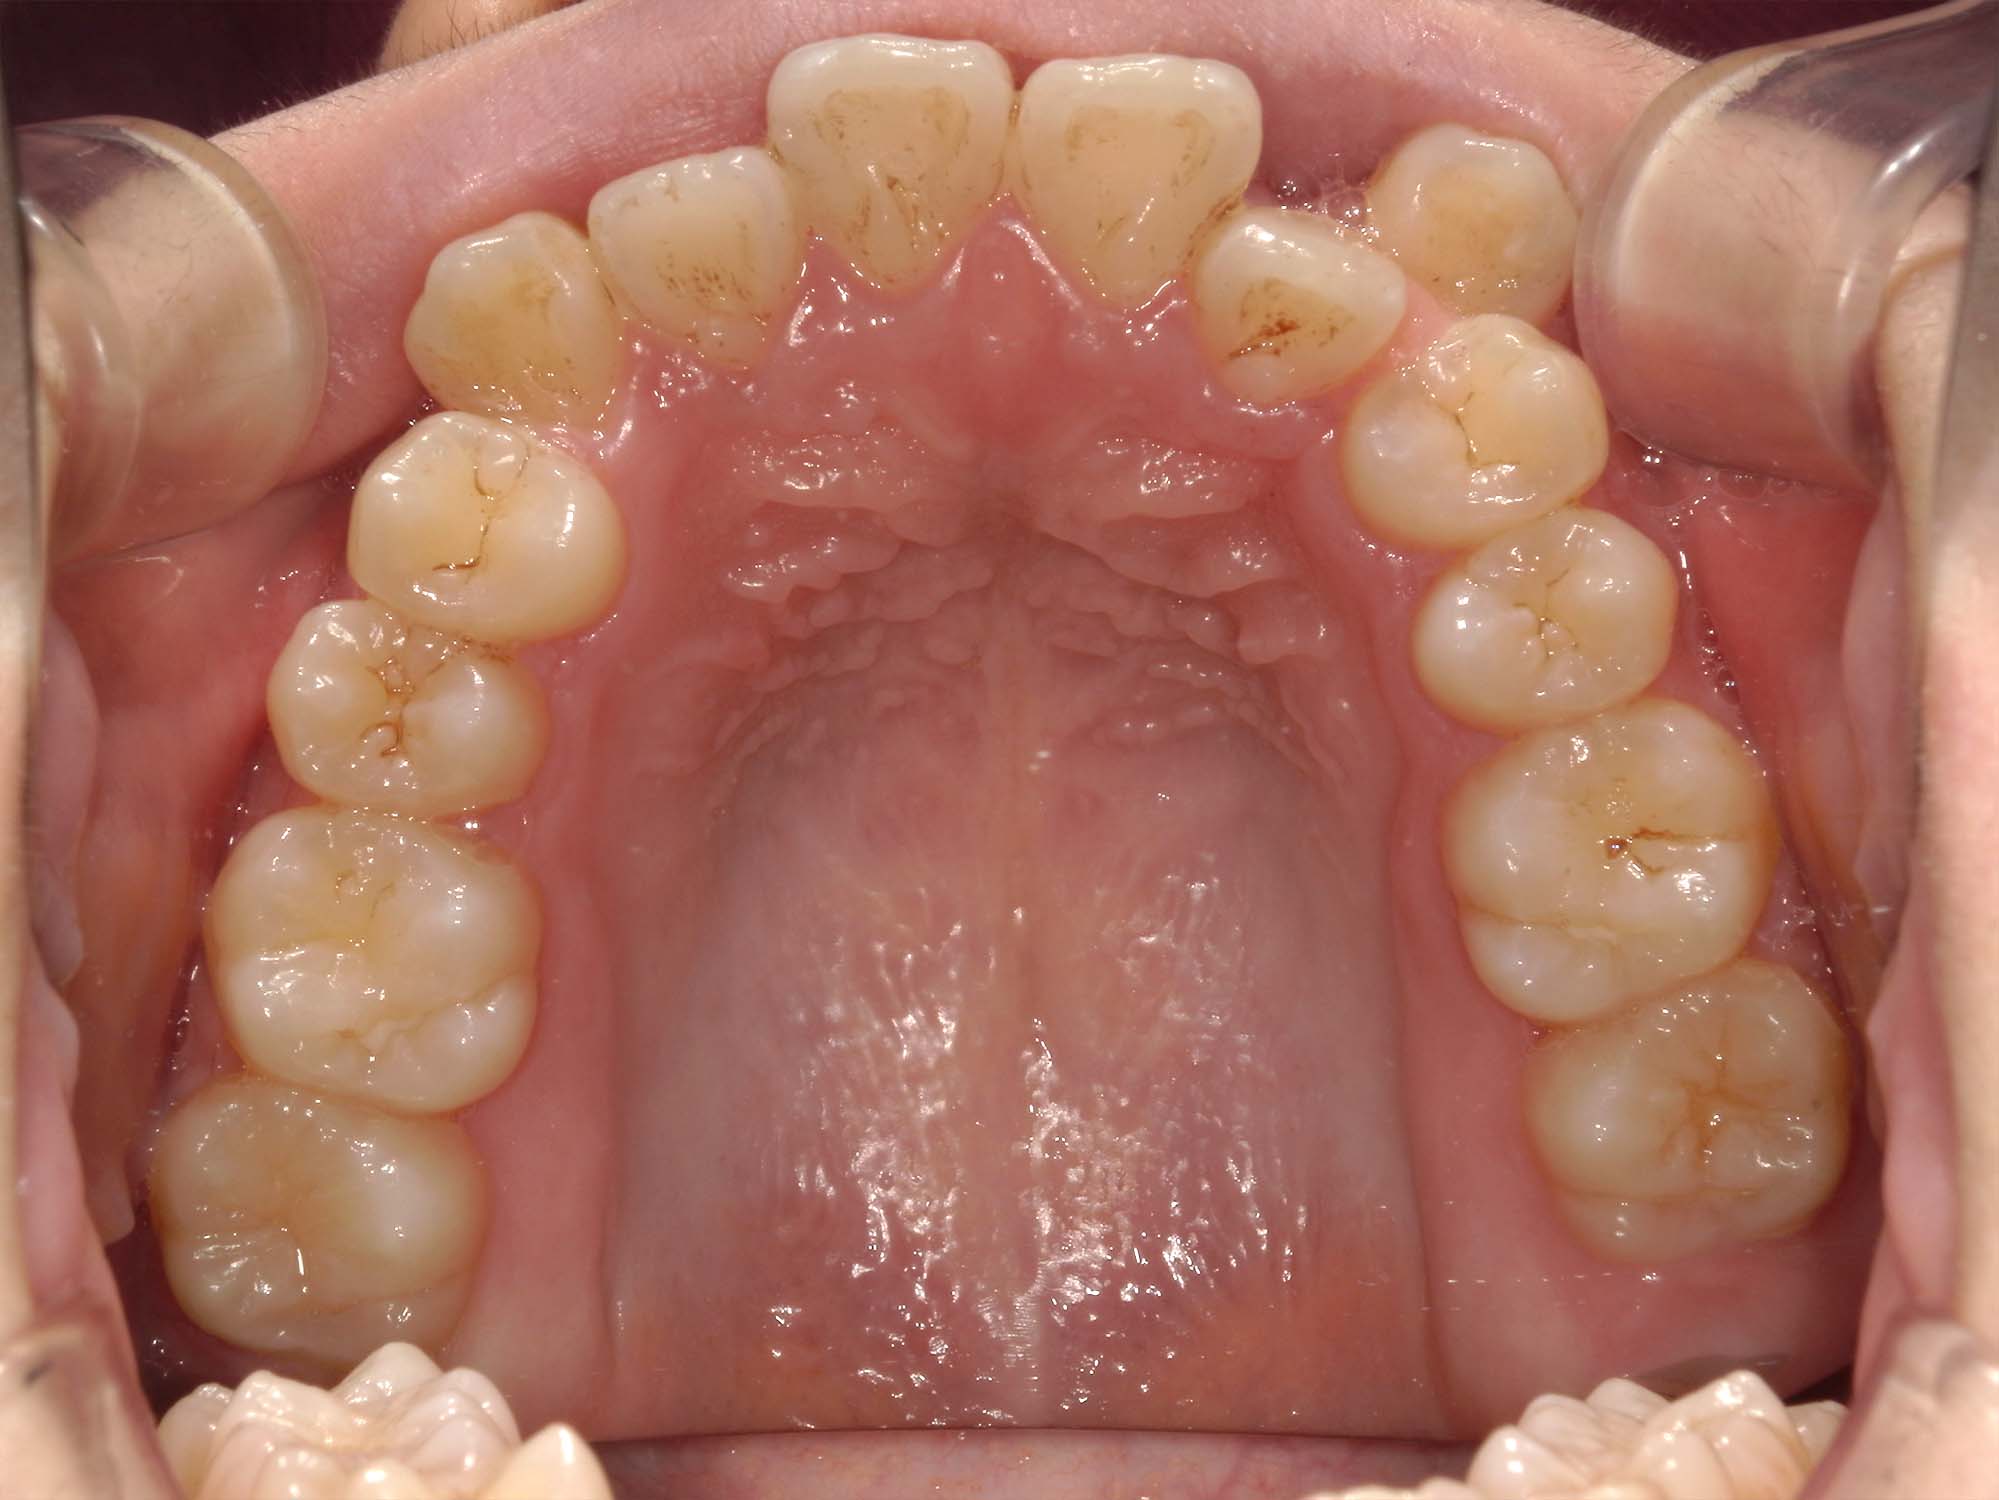

| 年齢・性別 | 25歳女性 |

|---|---|

| 主訴 | 前歯の歯並びの乱れ(叢生)を気にされて来院された25歳女性。咬み合わせや審美的な改善を希望されていました。 |

| 治療期間・回数 | 4年5ヶ月・30回 |

| 費用 | 1100,000円(税別) |